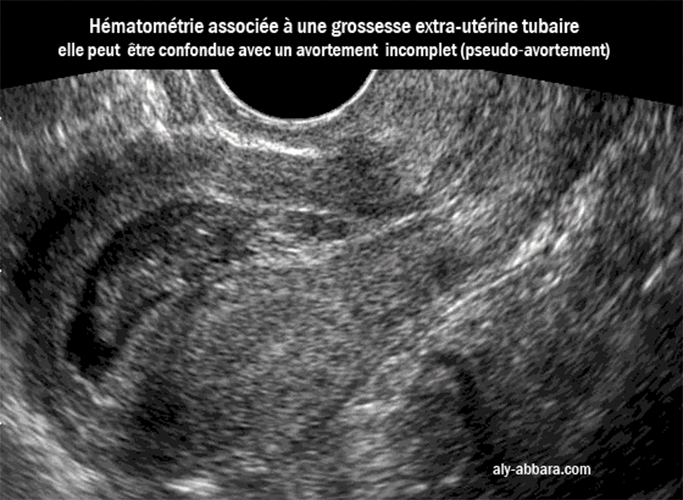

Grossesse extrautérine interstitielle tubaire avec un tableau clinicoéchographique pouvant. Le radiologue déplace la sonde de l'échographe sur la peau, au niveau du pubis, après l'application d'un gel facilitant la propagation des ultrasons Échographie transvaginale L'échographie transvaginale (ETV) en complé-ment à l'échographie pelvienne permet d'évaluer l'épaisseur de l'endomètre chez la patiente présen-tant des saignements anormaux